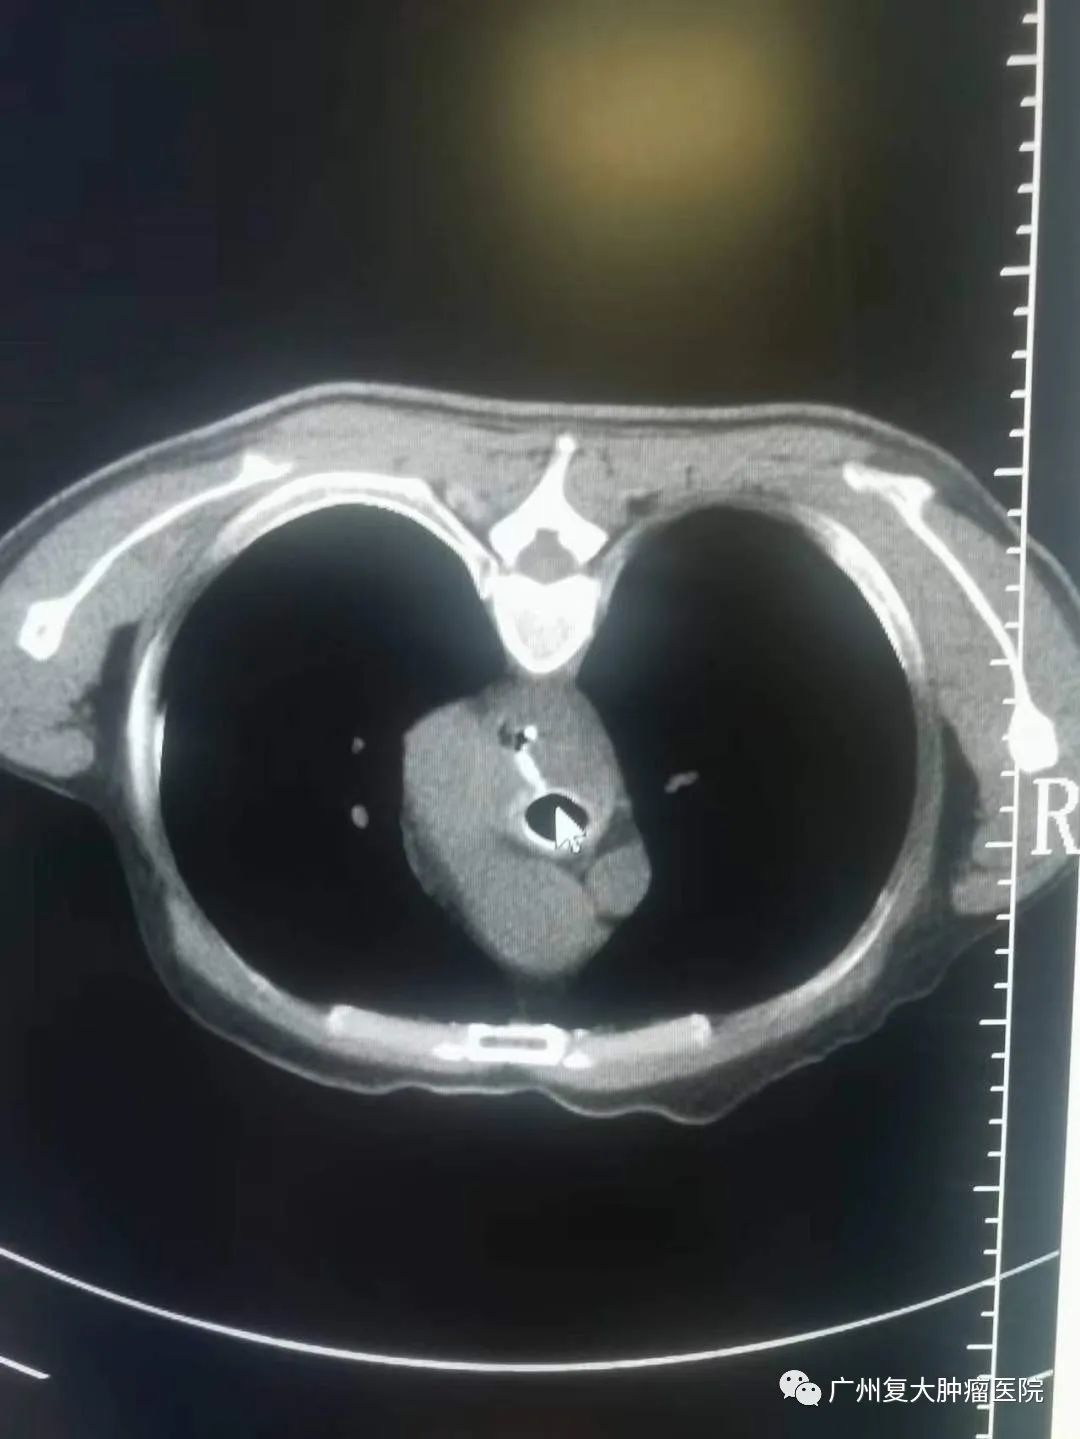

新年伊始,牛立志院长和介入科钟小军医生等医护人员在查房的过程中,收到一名食道癌患者满满的祝福。患者因食道癌并食道-气管瘘在多家大医院寻医问诊,但因带胃管两个多月,进食困难,精神萎靡,生活质量较差。为进一步诊疗,于年前28日晚来到我院,并在隔天完善相关检查后接受食道全覆膜支架置入。术后第一天便可以进食水,精神状态也明显好转。恰逢元旦来临,患者在院感受节日氛围的同时,身体状况也愈来愈好,对他们一家人来说,这不仅是最好的新年礼物,也让他们对新的一年充满新希望。为此,患者把自己亲手写的祝福送给医护人员,以表感谢之情。